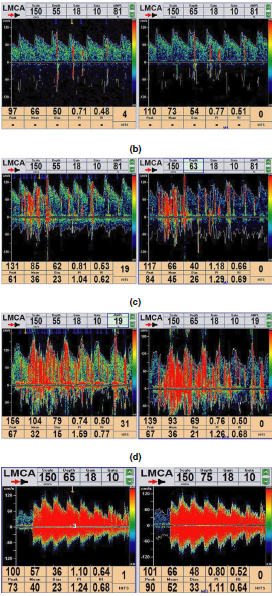

Methods: In this study, we enrolled consecutive migraineurs who underwent a structured,standardized questionnaire for family and personal history and for detailed migraine features. RLS was diagnosed based on a contrast enhancement transcranial Doppler (c-TCD) examination.